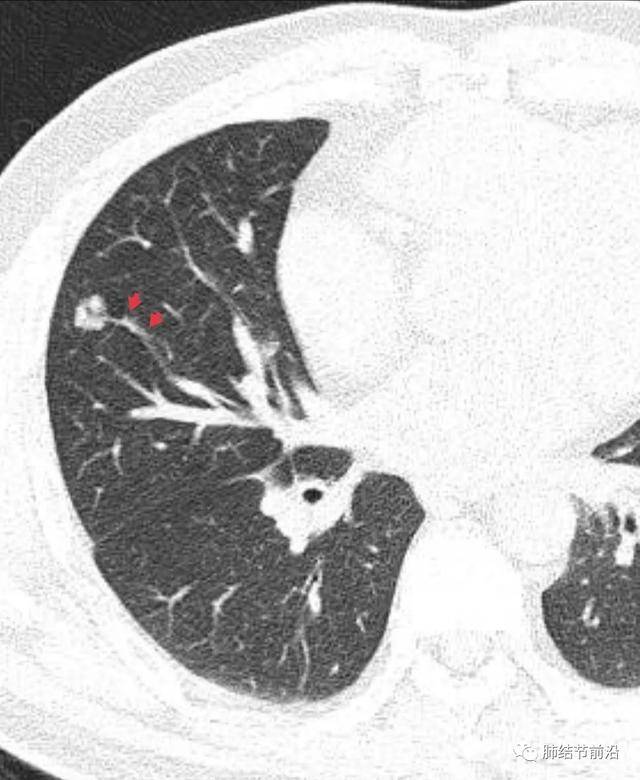

什么是肺結(jié)節(jié)呢?肺結(jié)節(jié)是指肺部出現(xiàn)的一種直徑小于或等于3厘米的圓形或近似圓形的病灶,大多數(shù)肺結(jié)節(jié)是良性的,只有一小部分可能是惡性的。

診斷肺結(jié)節(jié)主要依賴(lài)于醫(yī)學(xué)影像技術(shù),如X光、CT等,醫(yī)生會(huì)根據(jù)患者的病史、體征和影像學(xué)表現(xiàn)進(jìn)行綜合判斷,對(duì)于疑似惡性的結(jié)節(jié),可能需要進(jìn)行進(jìn)一步的檢查,如活檢等。